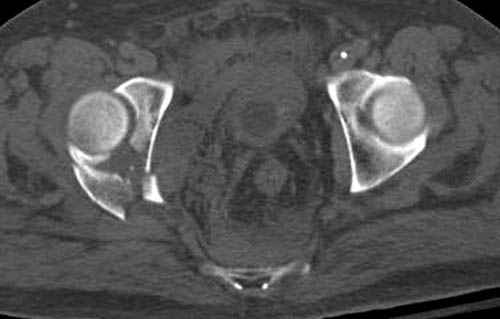

На седьмой день зафиксирован перелом ацетабулума через задний доступ. Перед операцией для профилактики DVT, IVC фильтер, также получает Lovenox.

По возможности вышлите снимки, сканы таза до

реконструкции, интраоперационные.

По снимку создается впечатление о высоком поперечном переломе, задней колонны, стенки; почему не пользовались *magic screw*?

Положение больного на животе или на боку?

Не хотелось отклонятся от основной темы, поэтому здесь краткие ответы..

Латеральное положение облегчает проведение тракции через вертел, за 5 мм стержень за вертел (грузом через тракционное приспособление), на обычном рентгенопрозрачном операционном столе, а для положения на животе, наверное, Judet Table более приемлем, потому что там имеется латеральное тракционное устроиство.

Там множество обычных 2.7 мм шурупов, потом идет фиксация основными пластинами.

Кава фильтр при переломах таза - это протокол или только для пациентов с политравмой?

Профилактику DVT и установку кава фильтер применям

почти у всех со множественными травмами, особенно тем, кто потенциально должны находится длительно без активного движения, тем более тем, кто страдает избытком веса.

В нашем протоколе в день операции делаем допплеровскую проверку сосудов, и в координации с сосудистыми хирургами установку фильтра до начала нашей операции, современные фильтры временные, можно удалить через несколько месяцев.

Полную нагрузку разрешаем в 12 недели, хотя движения в суставе с первых дней.

Снимки здесь....